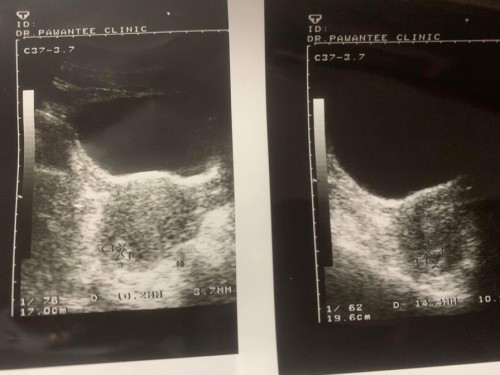

ตอนนี้ท้องได้ 6w ค่ะ ซาวแล้วเจอแต่ถุงตั้งครรภ์แต่ไมาเจอน้อง คุณหมอให้รออีก 2w แล้วไปซาวดูอีกครั้งถ้ายังไม่เจออาจจะต้องยุติการตั้งครรภ์ 😭😭😭 อาการตอนนี้มีปวดท้องคล้ายๆกับเวลาปวดประจำเดือนและพึ่งปวดเอวได้ 1-2 วันค่ะ 😭 มีใครเป็นเหมือนกันบ้างมั้ยคะ

เราไปตอน 5วีคได้ค่ะ ไปคลีนิก ปวดท้องหน่วงๆ มีเลือดซึมหน่อยๆ หมอบอกอาจจะหลุดไปแล้ว ให้มาใหม่ ใจเเม่นี่เเป้วไปเลยค่ะ เลยตัดสินใจไป รพ.อีกรอบ หมออธิบายดีมาก บอกว่าที่ปวดท้อง เลือดซึมเพราะ ตัวอ่อนฝังตัวค่ะ ล่ะที่ยังไม่เจอมันเป็นปกติค่ะ นัดอีกที 2 อาทิตย์ ซาวน์อีกรอบคือได้ยินเสียงหัวใจล่ะ สรุปฝากท้อง รพ.เลย ไม่ไปล่ะคลินิก ตอนนี้ก็ อีก 2วันครบ 35 วีคค่ะ😂

ใจเย็นค่ะๆ เราก็เป็น มีอาการเหมือนกันเลยปวดท้องคล้ายปวด ปจด แถมมีเลือดออก นึกว่าน้องไม่อยู่แล้ว 5สัปดาห์ไปเจอแต่ถุงเหมือนกัน กว่าจะเจอเกือบ9สัปดาห์ น้องยังเล็กมากค่ะ

บ้านนี้6wเกือบๆ7wซาวด์ผ่านช่องคลอดถึงจะเห็นค่ะ ซาวด์หน้าท้องยังไม่เห็นเลย น้องยังเล็กมากๆ มาเจอน้องพร้อมหัวใจเต้นผ่านการซาวด์หน้าท้องตอน8wค่ะ

เป็นเหมือนกันค่ะ หมอเลยนัดอีก 3w เลยเจอน้อง คุณหมอแจ้งว่า ตอน 6w น้องน่าจะตัวเล็กเลยยังไม่เห็น คุณแม่ทำใจให้สบายนะค่ะ รอบหน้าเจอน้องแน่นอน

เหมือนกันค่ะ 7 wk ไม่เจอน้อง ไปอีกที 9 wk หมอแจ้งภาวะท้องลม เพิ่งขูดมดลูกไปได้ 2 สัปดาห์ค่ะ ขอให้โชคดี เจอน้องในครั้งหน้านะคะ

ตอนนี้เรา 7 w มีเลือดออก ไปหาหมอ หมอไม่เจอน้อง เจอแต่ถุงไข่แดง หมอบอกว่าอาจจะท้องลม หมอนัดอีกที 1 wค่ะ ถ้ายังไม่เจอจริงๆ หมอว่าท้องลมค่ะ ตอนนี้แม่รู้สึกแย่มากๆค่ะ ได้แต่ขอพรให้ครั้งหน้าคุณหมอหาน้องเจอค่ะ😭😭😭

เป็นเหมือนกันค่ะ ตอนฝากครั้งแรก 6w ยังไม่เจอตัวน้อง พอหมอนัดรอบหน้า 12w ถึงเจอ น้องยังตัวจิ๋วเลยเจอแค่ถุงตั้งครรภ์ค่ะ